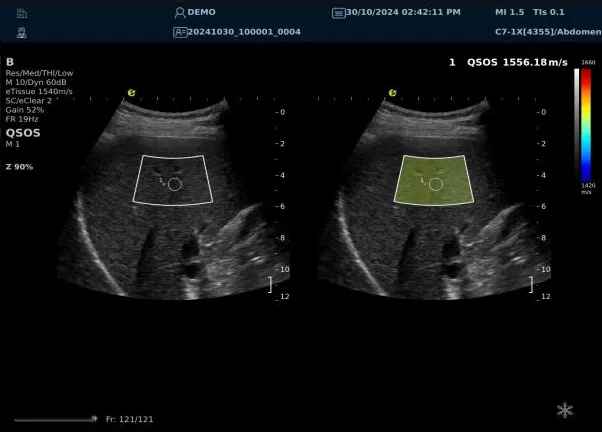

640.jpg123 (2).jpg可以设想,单位时间可发射的脉冲波越多、单位面积可发射的脉冲波越密集,得到的数据结果就越快、越多。也就是说,如果医生希望得到实时、大幅的声速定量图像,就需要超声系统具备“超快速”发射和接收的能力,新航娱乐医疗(ESI)ePascal东风系列超声平台的200+倍成像速度,成为了这项新技术得以临床应用的重要条件。

以上为应用声速定量成像技术检查肝脏的超声图像,图中在取样框内选择了三个测量区域,得出了各区域内的组织声速值以及声速衰减系数等结果。